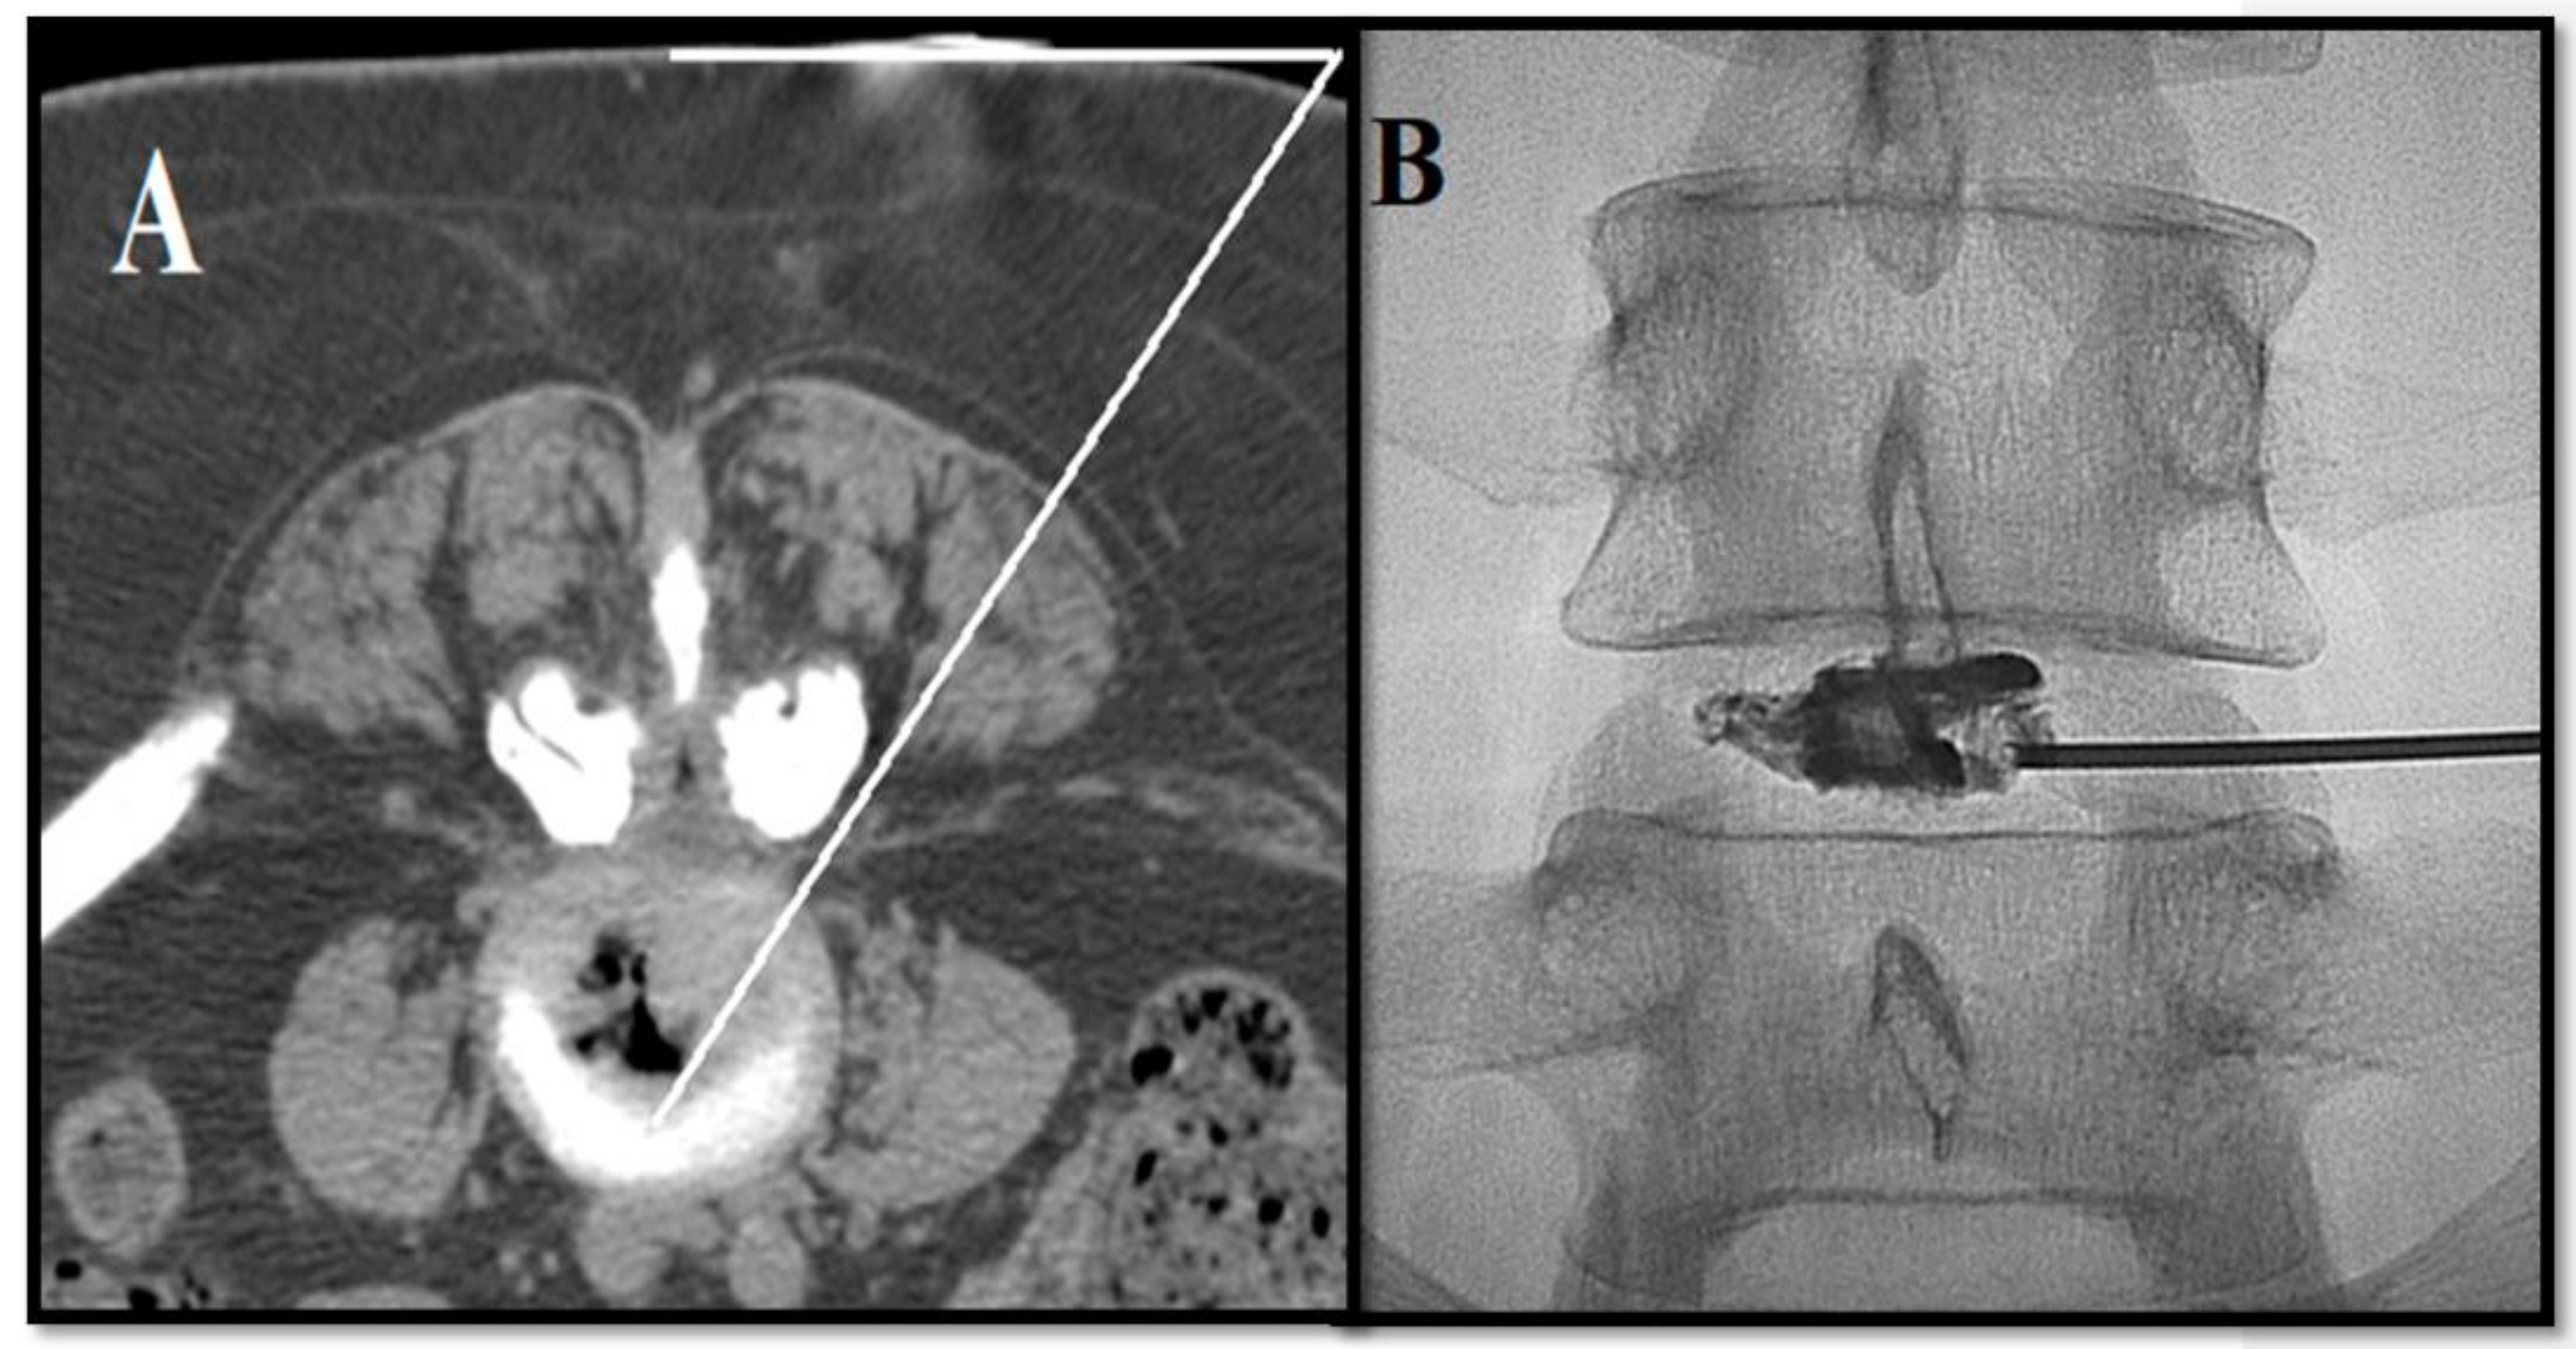

- Kelekis, A.; Filippiadis, D. Percutaneous treatment of cervical and lumbar herniated disc. Eur. J. Radiol. 2015, 84, 771–776. [Google Scholar] [CrossRef]

- Amoretti, N.; Huwart, L.; Marcy, P.Y.; Foti, P.; Hauger, O.; Boileau, P. CT-and fluoroscopy guided percutaneous discectomy for lumbar radiculopathy related to disc herniation: A comparative prospective study comparing lateral to medial herniated discs. Skelet. Radiol. 2013, 42, 49–53. [Google Scholar] [CrossRef]